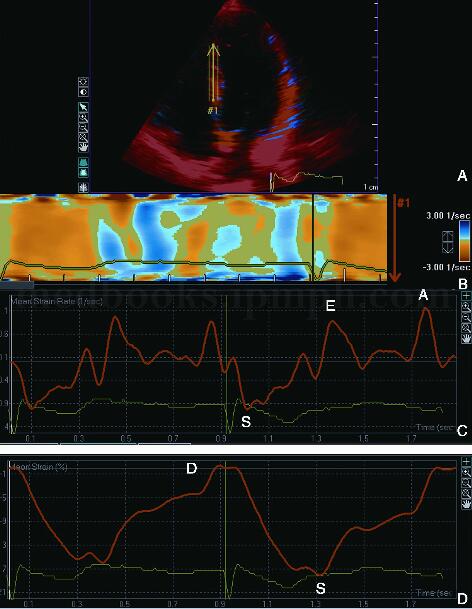

应变及应变率成像可实时评价心肌的变形,应变反映的是心肌变形的程度和心室几何形态的变化,应变率反映的是心肌局部收缩能力。显像方式有二维彩色图像、M型图像和应变及应变率‐时间曲线(图2‐1‐156)。初步临床应用表明应变及应变率成像是目前准确定量评价局部心肌功能和心肌存活的方法之一,其评价局部心肌缺血和心肌存活的敏感性和特异性均高于组织速度显像。与组织速度显像相似,明显的角度依赖性是其主要的局限性。

图2‐1‐156 正常人应变与应变率图像

A﹒心尖四腔切面组织速度彩色二维显像;B﹒间壁的彩色M型应变率图像;C﹒间壁的应变率‐时间曲线;D﹒间壁的应变‐时间曲线